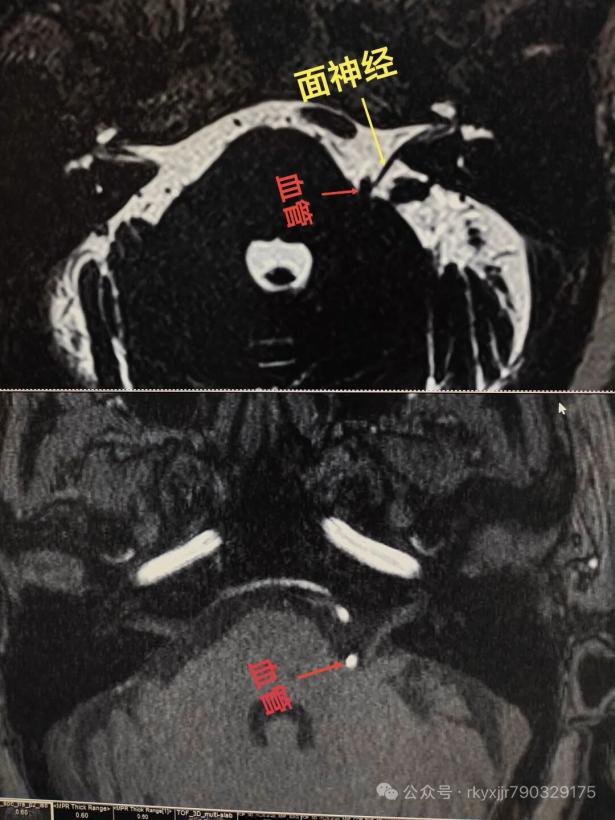

技术名称:3D-TOF MRTA(磁共振断层血管成像)(全称:三叉神经/面神经与血管关系磁共振成像)

技术简介:本技术是针对颅神经病变的无创、高分辨率专项检查技术。依托先进的3.0T磁共振平台,采用三维时间飞跃法(3D-TOF)及薄层重建技术,可清晰显示三叉神经、面神经等颅神经的细微走行,并精准捕捉神经与周围血管(如小脑上动脉、椎动脉)的空间毗邻关系。作为目前诊断神经血管压迫综合征的首选影像学方法,它能直观呈现血管是否对神经造成压迫、移位或变形,为临床判断病因、制定微血管减压术方案提供“可视化”的金标准依据,具有无创伤、无需造影剂、定位精准的显著优势。